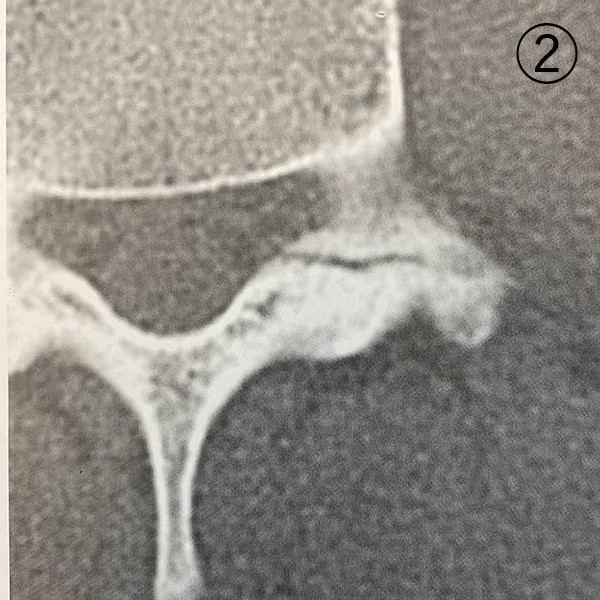

レントゲン写真

1ヶ月後のCT画像